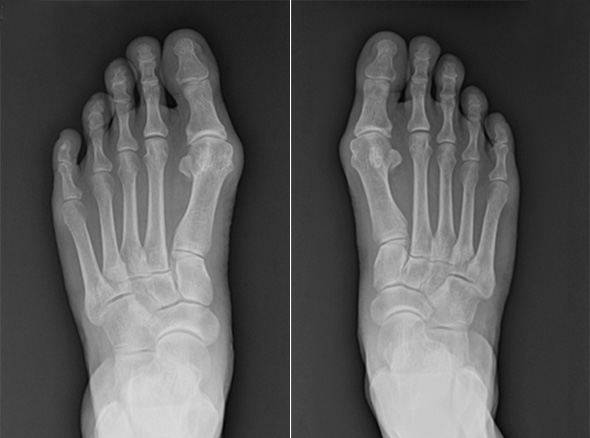

MICA, minimally invasive Chevron & Akin osteotomy

비절개 무지외반 교정술을 시행하고 나서는 획기적으로 회복 속도가 빨라졌고,

비절개 무지외반 교정술은 나사와 절골침이 들어갈 정도의 작은 구멍만 내고 하는 수술로 흉터는 낫고 나서는

거의 점처럼 보입니다. 수술 다음 날부터 큰 통증 없이 딛고 걸어 다니는 것도 가능합니다.